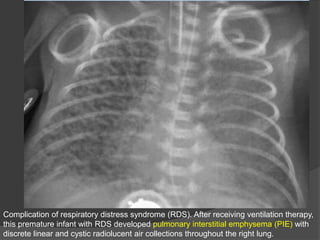

Complication of respiratory distress syndrome (RDS). After receiving ventilation therapy,

this premature infant with RDS developed pulmonary interstitial emphysema (PIE) with

discrete linear and cystic radiolucent air collections throughout the right lung.

Complication of respiratorydistress syndrome (RDS). After receiving ventilation therapy, this premature infant with RDS developed pulmonary interstitial emphysema (PIE) with discrete linear and cystic radiolucent air collections throughout the right lung.